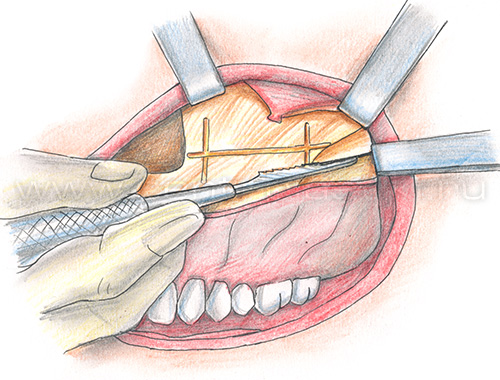

Остеотомия верхней челюстиПоказания Коррекция аномалий развития верхней челюсти (микрогнатия, ретрогнатия верхней челюсти). Остеотомию на верхней челюсти проводят как этап ортодонтического лечения. Операция Остеотомия верхней челюсти выполняется внутриротовым доступом под эндотрахеальным наркозом, выполняется разрез слизистой оболочки полости рта и надкостницы, разрез производят несколько выше переходной складки верхней челюсти от 7 до 7 зубов. Края раны раздвигаются, тем самым осуществляется доступ к передней стенке верхней челюсти.  На передних и боковых стенках верхней челюсти слева и справа производятся разметки линий распилов.  Специальными пилками проводится остеотомия по разметкам.  Затем отделяется распиленный фрагмент и перемещается в заранее выбранное положение.   Фиксация перемещенного фрагмента в новом положении осуществляется титановыми мини-пластинками.  Длительность Операция занимает от 1,5 до 3 часов и проводится под наркозом. В течение 1 месяца после лечения сохраняется отечность мягких тканей лица, может отмечаться нарушение чувствительности верхней губы и щек, чувствительность восстанавливается самопроизвольно через некоторое время. В ряде случаев после операции для обеспечения хорошего срастания костей проводят межчелюстное шинирование , верхняя и нижняя челюсти фиксируются друг к другу специальными приспособлениями, так что полное открытие рта невозможно. В этот период (2-3 недели) возможно питание только протертой и жидкой пищей. После операции остеотомии верхней челюстиВ послеоперационном периоде возможно ношение ортодонтической брекет системы для правильного смыкания зубных рядов верхней и нижней челюстей. Реабилитационный период В течение 1-3 суток после операции рекомендовано нахождение в стационаре под наблюдением медицинского персонала (длительность нахождения в стационаре может быть продлена до 10 суток в зависимости от течения послеоперационного периода). Длительность реабилитационного периода зависит от восстановительных способностей организма. Эффективность Окончательный результат операции можно наблюдать через 3-6 месяцев. В послеоперационном периоде могут сохраняться отеки в течение 2-4 недель, в зависимости от индивидуальных особенностей восстановление протекает с разной скоростью. |